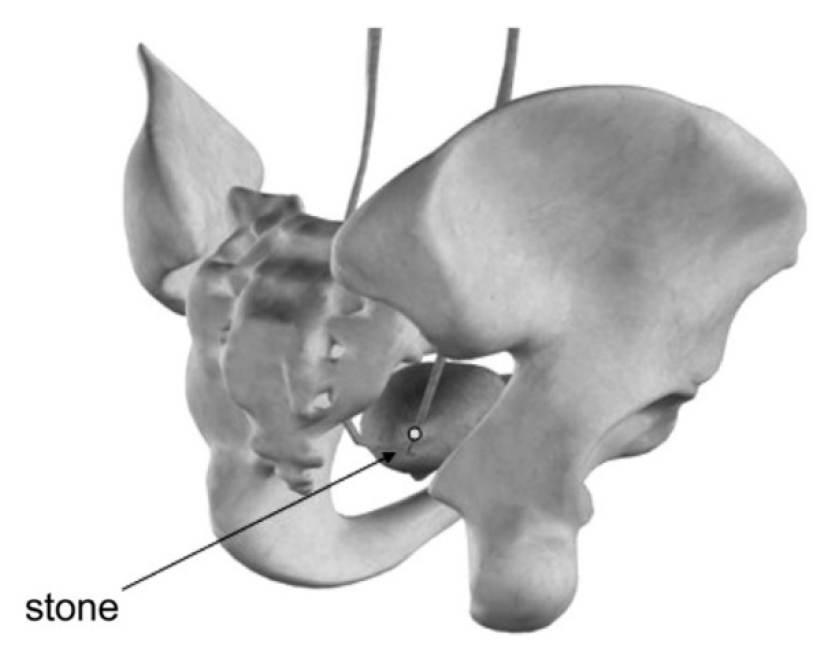

기술의 지속적인 발전과 경험의 축적으로 충격파가 대좌골공(greater sciatic foramen) 및 소좌골공(lesser sciatic foramen)과 같은 골반뼈의 틈을 통해 하부요관결석에 도달하여 결석을 파쇄 할 수 있다는 연구결과들이 최근 보고되고 있다 [그림 1]. 여러 연구 결과들에 따르면, 앙와위(supine position)에서 충격파는 대둔근(gluteus maximus muscle)을 따라 대좌골공을 통해 전달되어 골반뼈를 피할 수 있고, 장내 가스로 인한 충격파 감쇄 효과를 최소화할 수 있어, 복와위 보다 더 효과적이고 안전하다고 알려지고 있다.

결석을 조준할 때에는 결석의 위치와 환자의 특성, 그리고 쇄석기의 종류에 따라 환자의 자세를 적절히 조절하여 최적의 충격파 경로를 선택하여야 한다. 하부요관결석의 경우 골반뼈의 골격구조가 충격파의 경로를 방해할 수 있어, 전통적으로 복와위를 선호하고 있다. 하지만 복부 방향에서 충격파를 전달하는 경우 장내 가스로 인해 충격파 에너지의 상당 부분이 소멸될 수 있고, 장천공의 위험이 있다. 그 외 수정된 복와위 자세(modified prone position)나 말타는 자세로 시행하는 방법(straddle or horse-riding position) 등을 제안하여 보다 높은 성공율을 보고하기도 하였다 [9,10]. 최근에는 앙와위에서 대둔근을 따라 대좌골공을 통한 경둔근 접근법(trans-gluteal approach)이 충격파 전달에 더욱 효과적이고 안전하다는 연구결과들이 있어, 그 장점에 대해 소개해 보고자 한다.